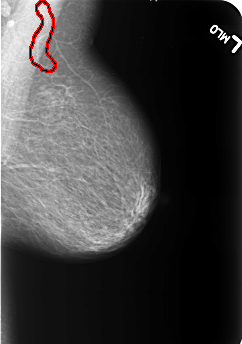

B_3233_1.LEFT_MLO

LEFT_MLO LINES 5496 PIXELS_PER_LINE 3872 BITS_PER_PIXEL 12 RESOLUTION 50 OVERLAY

FILE: B_3233_1.LEFT_MLO.OVERLAY

TOTAL_ABNORMALITIES 1

ABNORMALITY 1

LESION_TYPE CALCIFICATION TYPE VASCULAR DISTRIBUTION N/A

ASSESSMENT 2

SUBTLETY 4

PATHOLOGY BENIGN_WITHOUT_CALLBACK

TOTAL_OUTLINES 1

BOUNDARY